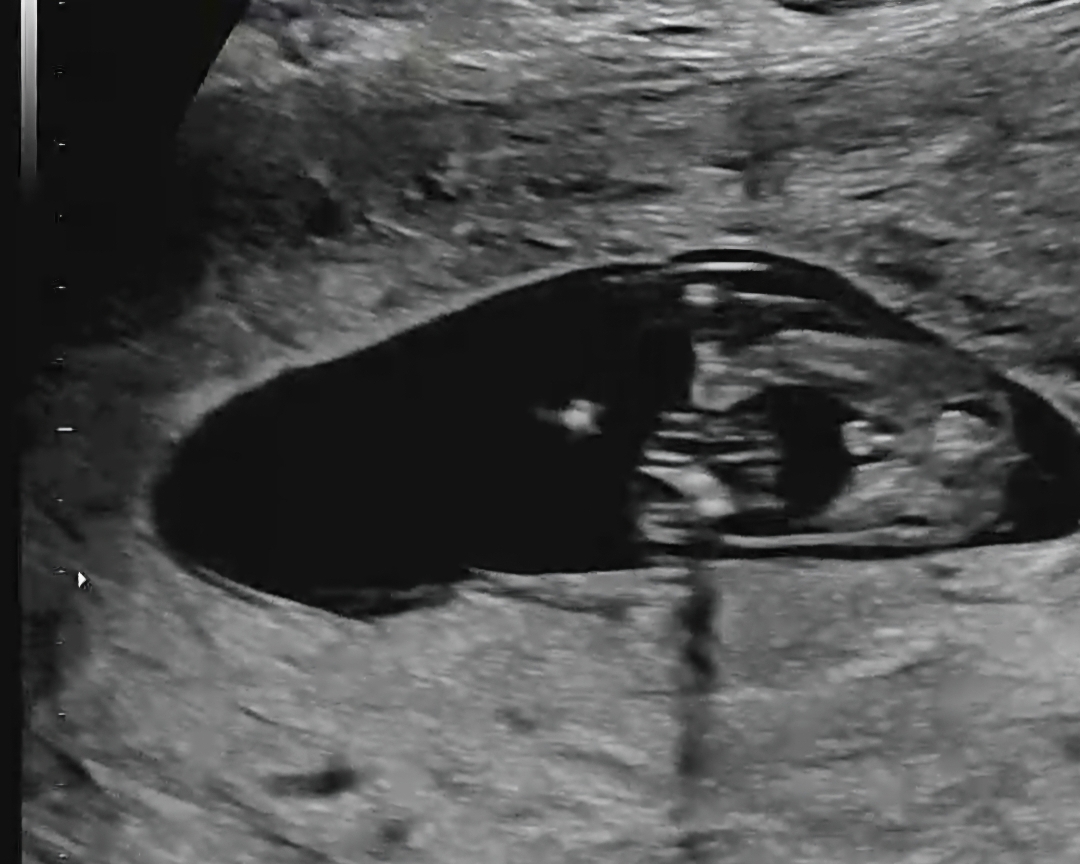

13주2일 초음파예요 ~성별 너무 궁금해요ㅠㅠ